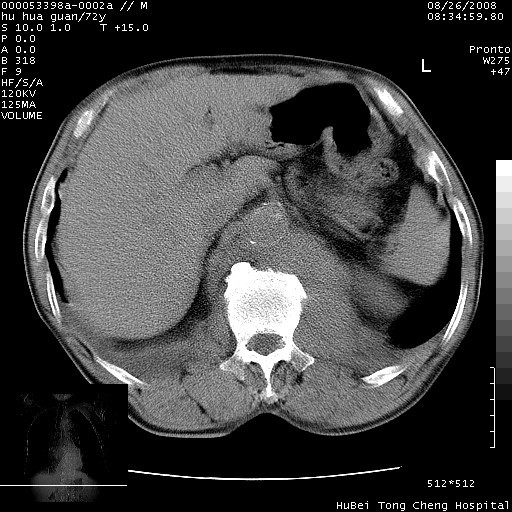

降主动脉前移位,后纵隔占位

后纵隔占位,降主动脉前移位;双侧胸腔积液;应排外食管病变侵犯血管可能;

可以明确的说。肯定不是主动脉夹层破裂出血!考虑为淋巴瘤或间叶组织来源的恶性肿瘤可能性大。右肺小结节建议薄层观察,如能发现恶性征象,那椎前改变就考虑为转移所致。至于双侧少量胸水乃静脉血回流受阻所致。

考虑胸主动脉下段夹层破裂。

考慮夾層動脈瘤破裂可能,建議增強掃描。